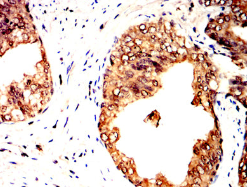

MTDH Mouse Monoclonal antibody[8A4B1]

IHC    1/200 - 1/1000